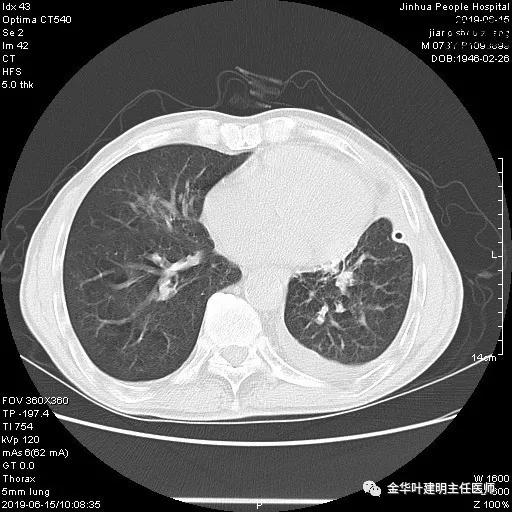

患者,男性,73岁,金华人。因“咳嗽咳痰伴胸闷2月,检查确诊左肺癌1周”入院。气管镜: 气管支气管内较多脓性分泌物,左肺上叶前段管腔新生物,局部活检、毛刷。气管镜病理:(左肺活检)鳞癌。阅胸部CT见左上叶开口处新生物,考虑需左上叶袖式切除及淋巴结清扫。具体CT表现如下:

6.15上午:24小时胸管引流出血性液250ml;复查胸部CT示: